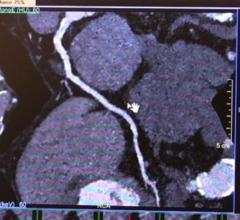

John Stevens, chairman and CEO of HeartFlow, explains his company's computed tomography (CT)-based fractional flow ...